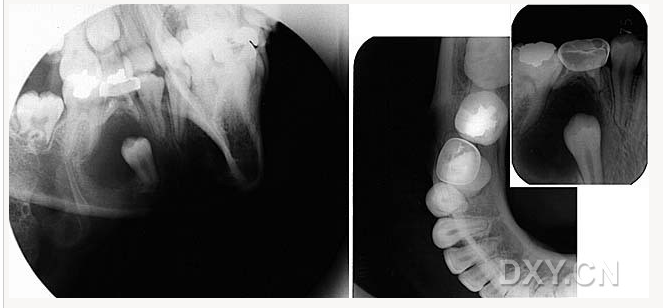

牙源性鈣化囊腫

牙瘤!

牙源性鈣化囊腫    牙瘤!

牙瘤